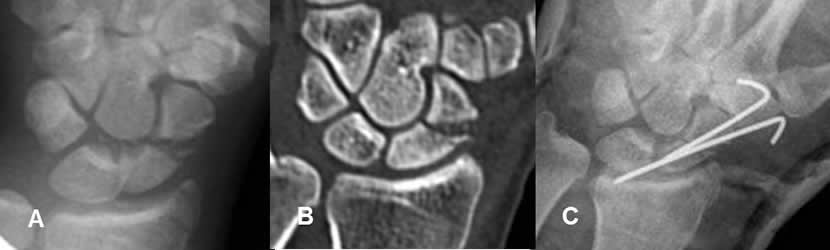

Fig 109. Desplazamiento del material.

A: Rx AP y B: TAC reconstrucción coronal. Fractura transversa y diastasada, en el tercio medio del escafoides.

C: Rx AP. Reducción cerrada con agujas. El extremo de una de ellas, tiene localización intra-articular.